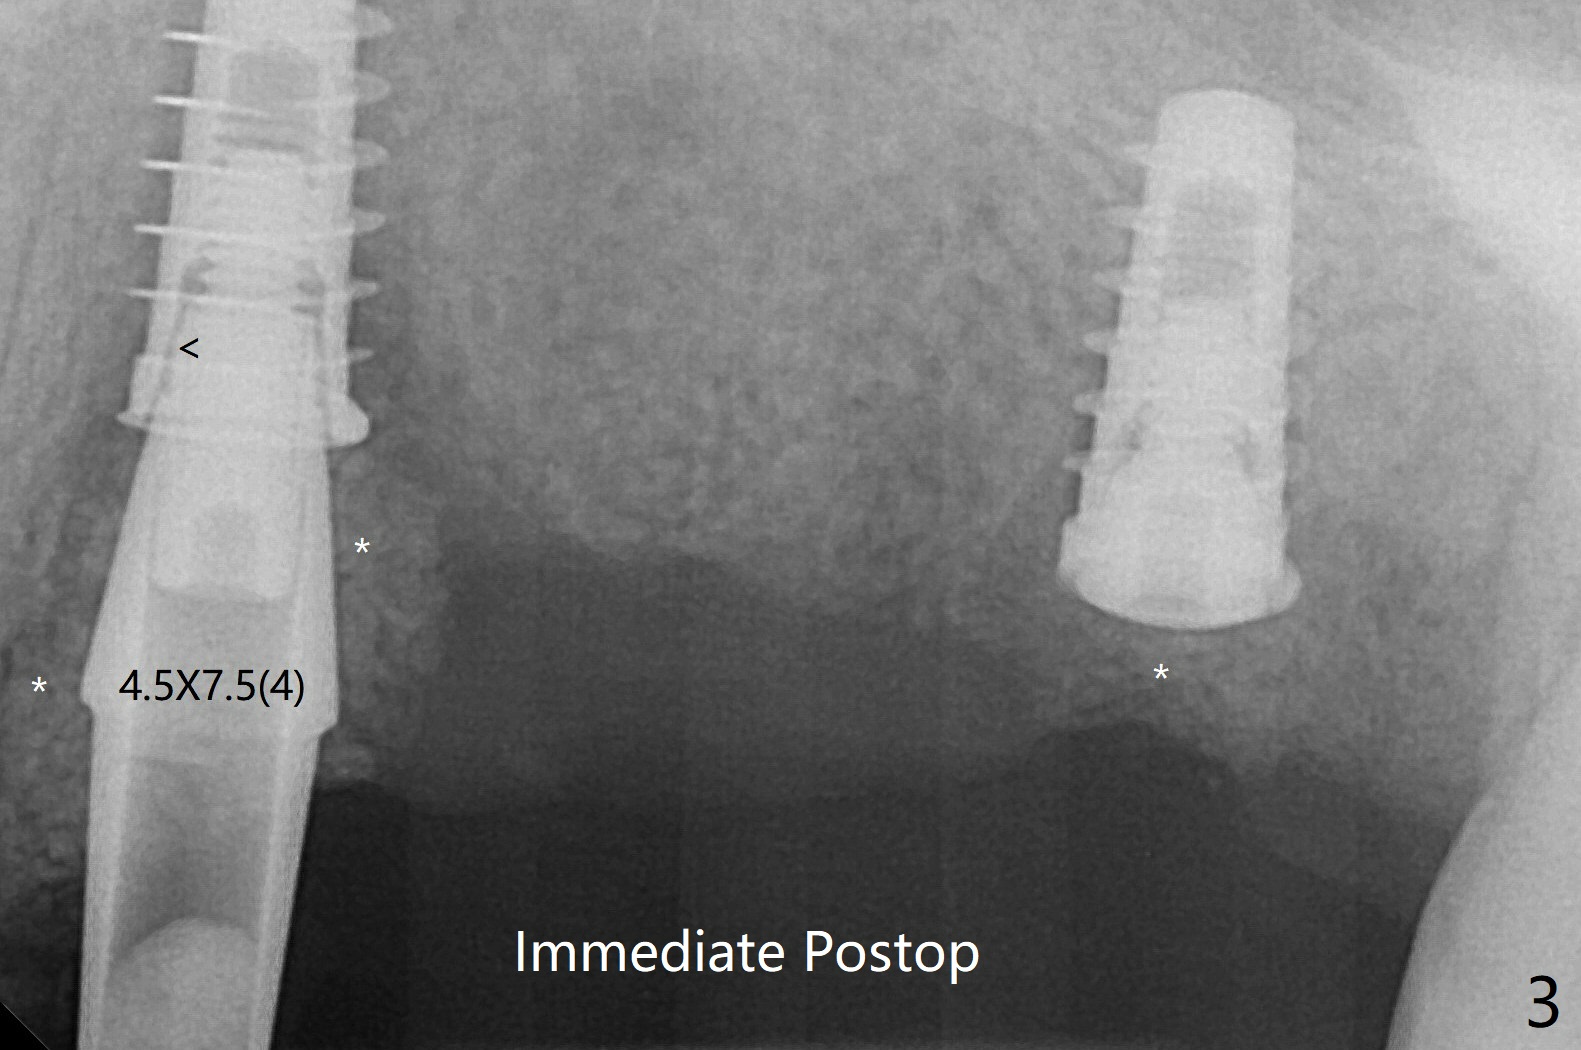

Sticky bone is placed to bury the implant at #14 (Fig.3 *). After placement (incomplete, Fig.3 <) of a 4.5x7.5(4) mm pair abutment, setting acrylic is applied around the abutment, over the bone graft at #14 (to prevent loss) and pressed into the undercuts of the proximal surfaces of the neighboring teeth for retention (Fig.4). The bone/implant gap reduces at #13 five months postop (Fig.7 (complete abutment seating)). There is no implant thread exposure at #13 (immediate), while minor exposure mesial to #15 (delayed).